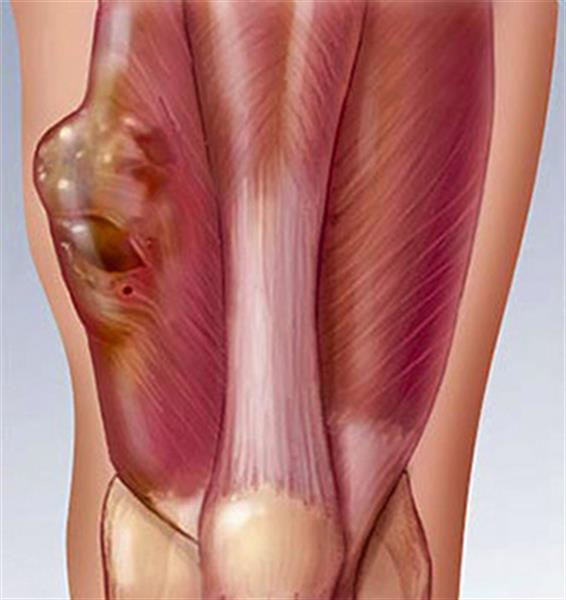

تومورها و کیست های سرطان دست.